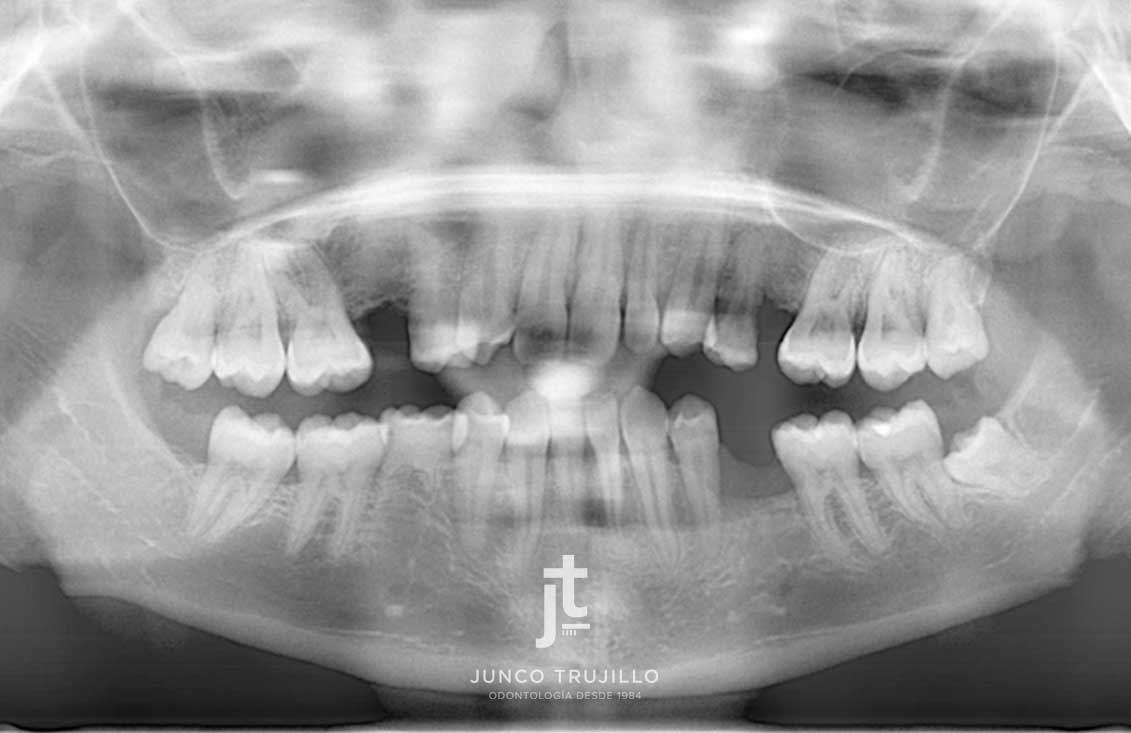

En nuestra clínica realizamos un estudio personalizado con radiografías y escáner 3D para planificar cada tratamiento con precisión. Los Implantes en Palencia permiten recuperar la capacidad de masticar con normalidad, mejorar la pronunciación y evitar la pérdida ósea que se produce tras la ausencia dental. Además, ayudan a mantener la armonía facial y la salud del resto de piezas dentales, evitando que se desplacen.

Casos de implantes